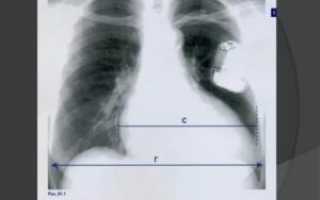

Достоверная визуальная диагностика плевральных шварт возможна только если соединительно-тканные образования больше 1 см в толщину. В противном случае тень от спаек накладывается на ткань легкого и не видна на рентгенограмме. При указании на характерные жалобы, которые возникли и сохраняются после перенесенного плеврита, требуется проведение дополнительных исследований таких, как:

- рентгенография динамическая (на вдохе и выдохе), в двух проекциях (прямой, боковой);

При тотальных швартах наблюдается деформация грудной клетки, сужение межреберных промежутков, смещение средостения в больную сторону, искривление позвоночника в здоровую сторону.